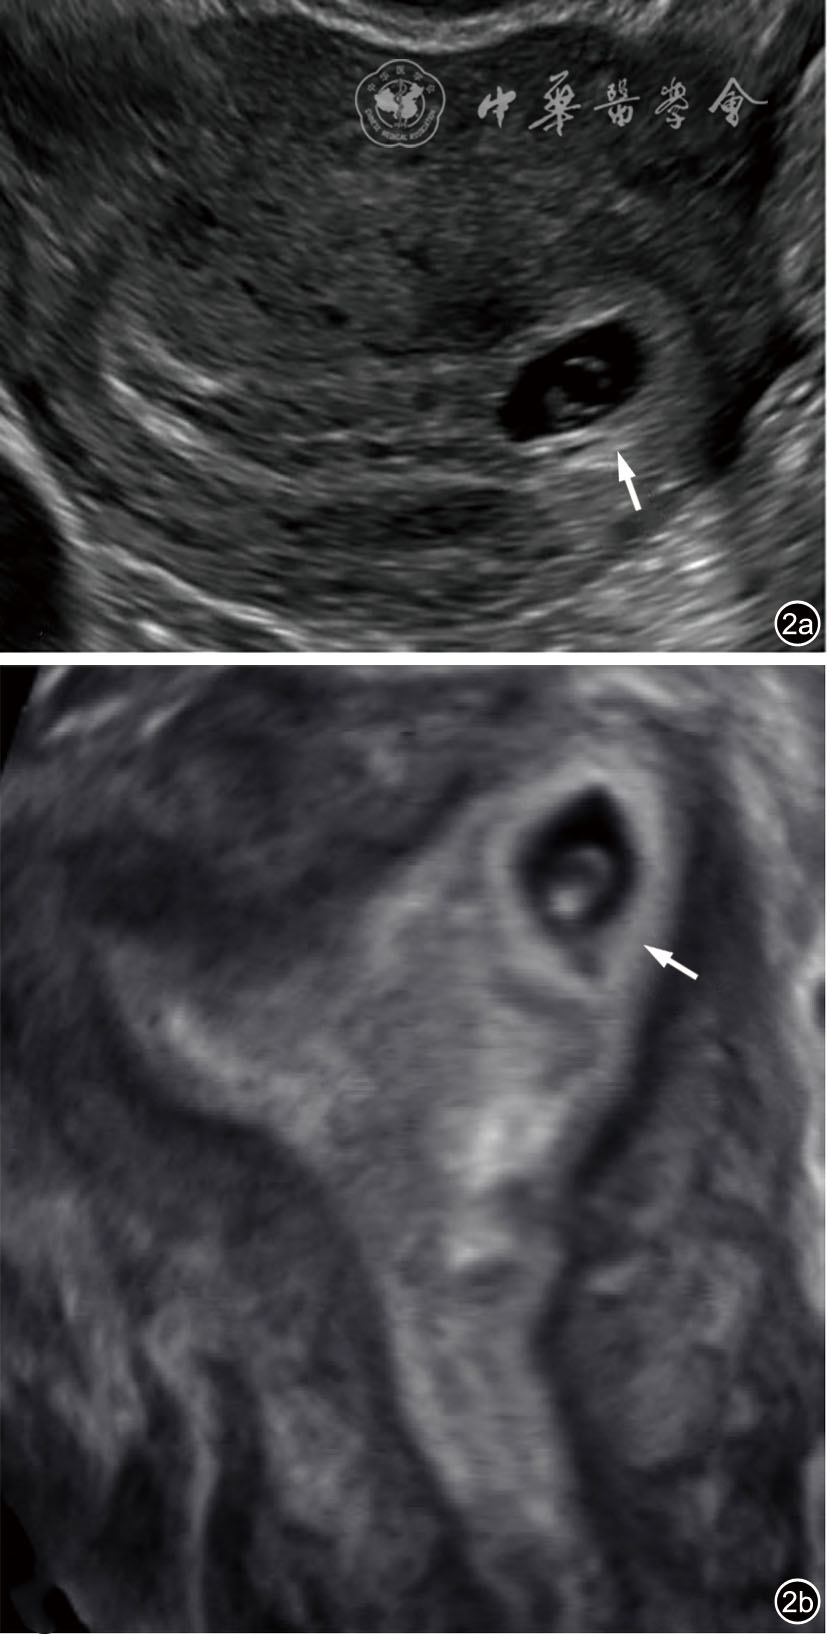

2.输卵管间质部异位妊娠:输卵管间质部异位妊娠较罕见,指受精卵着床于输卵管间质部(嵌入子宫肌壁内的输卵管近端部分)(图4)。超声诊断要点包括:(1)子宫与妊娠囊间滑动征阴性;(2)三维冠状切面重建图像显示子宫肌层部分包绕妊娠囊(妊娠囊周边子宫肌层组织呈“爪形征”),或子宫内膜与妊娠囊间可见薄层肌层组织;(3)间质线征仅偶见(图5),但该征象诊断输卵管间质部异位妊娠特异度较高。应避免使用‘宫角妊娠’或‘宫角异位妊娠’。

图4 输卵管间质部异位妊娠超声图像。图a为经阴道超声横切面灰阶图像,图b为三维超声冠状面重建图像。29岁孕妇(孕5周3天)的妊娠囊(测量游标)与子宫内膜(*)之间存在肌层组织(实线箭头),肌层组织的“爪形征”(虚线箭头)证实妊娠着床于输卵管间质部,提示为输卵管间质部异位妊娠。应避免使用‘宫角妊娠’或‘宫角异位妊娠’。三维超声冠状面重建可更清晰显示妊娠囊与子宫内膜分离,符合输卵管间质部异位妊娠(图4译自参考文献[1])

图5 间质线征超声图像。图为33岁孕妇(孕6周0天)经阴道超声横切面灰阶图像,显示右侧输卵管间质部异位妊娠(实线箭头)。除输卵管间质部异位妊娠特征性超声表现外,另可见一纤细高回声线(虚线箭头)连接子宫内膜与异位妊娠囊,为“间质线征”(图5译自参考文献[1])